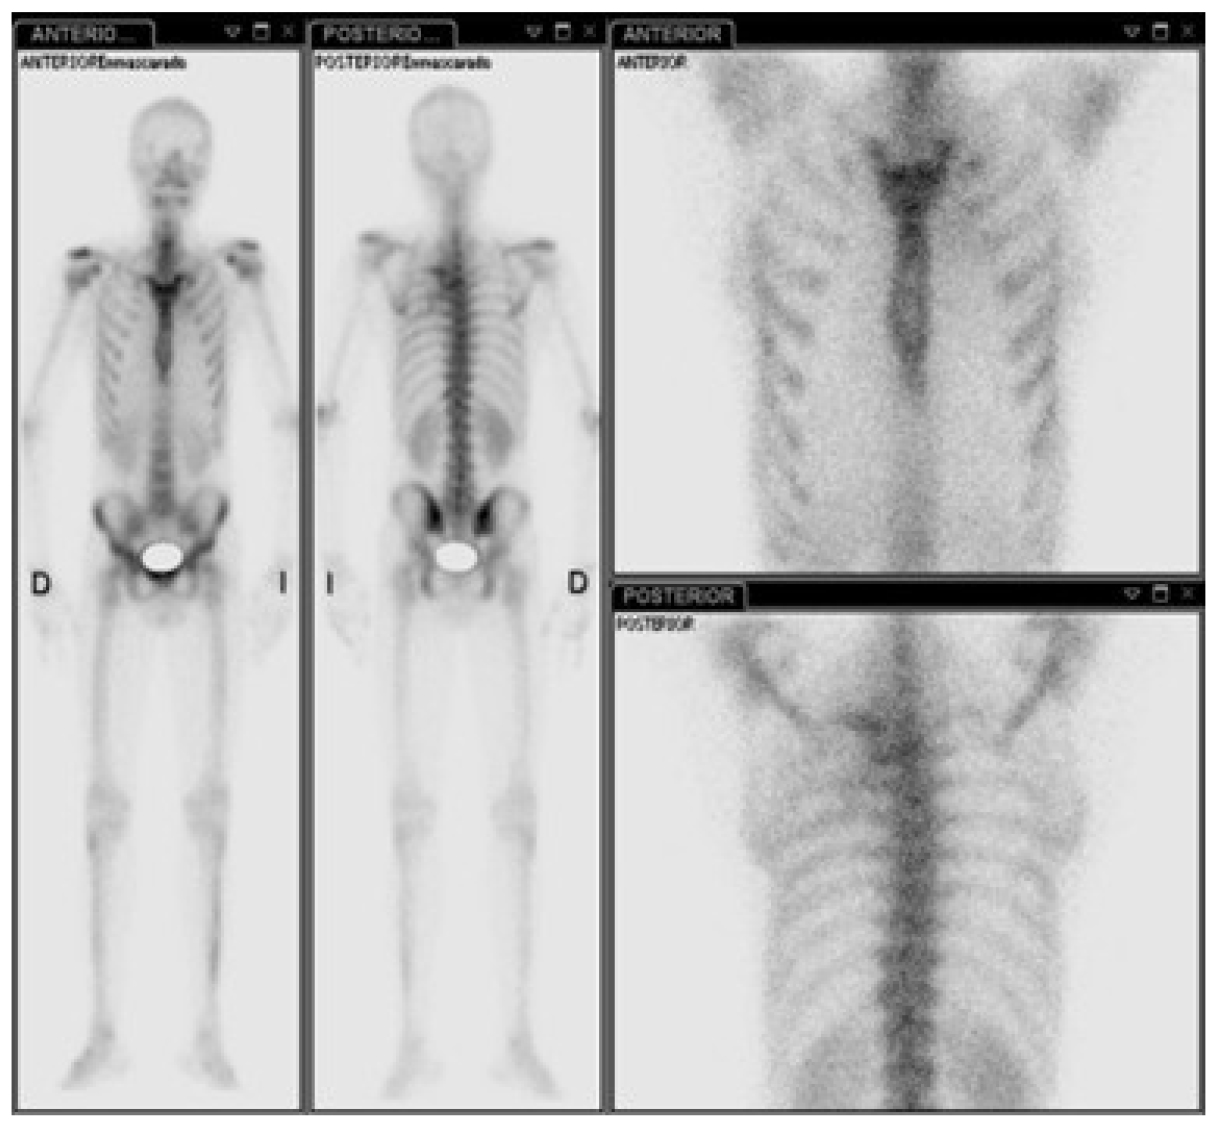

Para completar el abordaje, se le realizó al paciente una gammagrafía ósea que evidenció un tumor dependiente de vértebras torácicas que infiltraba el pulmón izquierdo y se introducía en el foramen vertebral de D3-D4, D4-D5, además de metástasis en los arcos costales cuarto y quinto izquierdos (figura 10).

Figura 10. Gammagrafía ósea vértebras D3-D4, D4-D5 con infiltración en pulmón izquierdo y arcos costales 4to y 5to izquierdos.

Gammagrafía ósea

El TOCG produce una mayor absorción de radiofármacos como tecnio-99m. El patrón de aumento de la captación puede ser difuso (40 %) o periférico, con poca actividad central (60 %). Los patrones extendidos de captación de radiactividad, más allá de los márgenes del tumor, impiden una definición precisa de la extensión intramedular. Puede ocurrir un aumento de la captación en el hueso a través de la articulación adyacente y en otras articulaciones de la misma extremidad no afectadas por el tumor. Por lo tanto, el papel de la gammagrafía ósea en la TOCG es limitado, porque es inespecífico y poco fiable para definir la extensión del tumor. Sin embargo, es útil para evaluar al paciente raro con TOCG multicéntrico o metastásico (13).